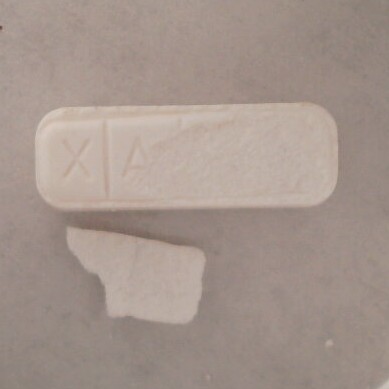

Fentanyl: PositiveBenzodiazepine: NegativeNotes: Vancouver, BC 01/18/2025 Category: DepressantDescription: White Pressed PillSold as: AlprazolamResult: Microcrystalline Cellulose Uncertain Oil

Fentanyl: NegativeBenzodiazepine: PositiveNotes: Imprint: XANAX / 2Vancouver, BC 01/18/2025 Category: PsychedelicDescription: Light Green CrystalSold as: MDMAResult: Fentanyl: NegativeNotes: Vancouver, BC 01/18/2025 Category: PsychedelicDescription: Green CrystalSold as: MDMAResult: Fentanyl: NegativeNotes: Vancouver, BC 01/18/2025 Category: OpioidDescription: Orange GranulesSold as: DownResult: Caffeine Desalkylgidazepam Ortho-Methylfentanyl Erythritol